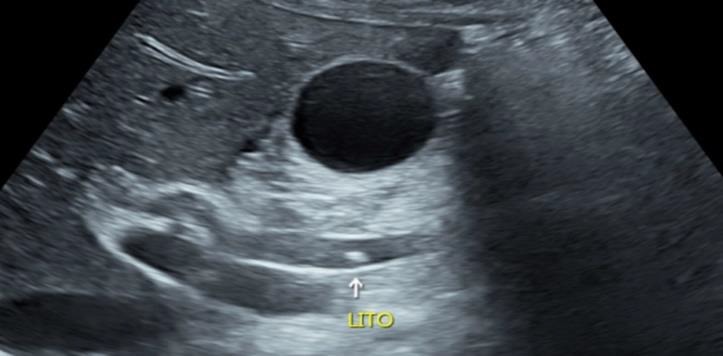

• Ecografia de vias biliares.